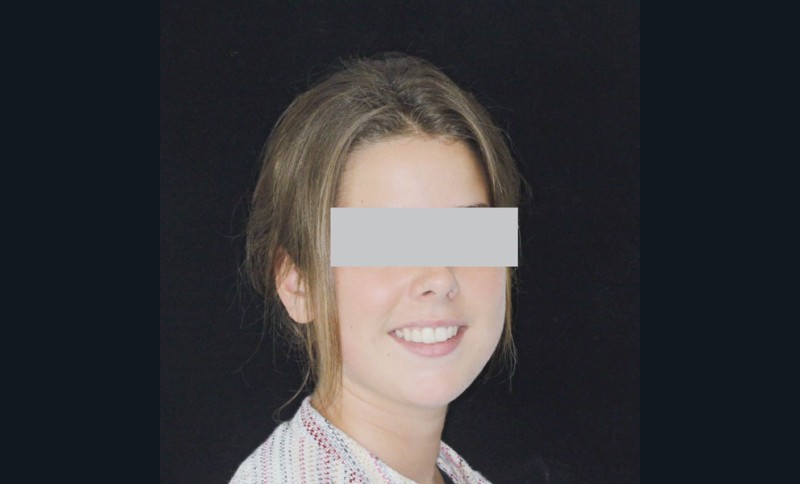

Ce cas a été conjointement suivi par les Drs Le Gall, Bachet et Dameron.